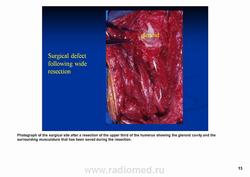

Рентгенологически выявляют в очаге деструкции участки обызвествления в виде крапчатости; кортикальный слой с признаками эрозии со стороны эндоста и истончения; размеры опухоли более 4 см; периостальная реакция слабо выражена или отсутствует; может наблюдаться деструкция кортикальной кости и наличие мягкотканного компонента; в длинных костях локализуется чаще в метафизах и диафизах; интенсивное внутрикостномозговое распространение.